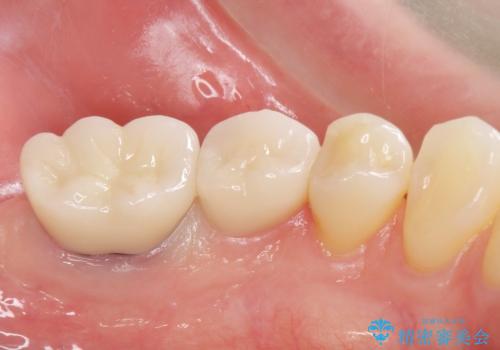

銀歯のやりかえ。

- 銀歯のやりかえ希望の患者様です。

患者様と話し合った結果、中の土台は外さず、被せ物のみのやりかえとなりました。

- ジルコニアクラウン・仮歯 12.1万円費用は治療当時の料金となります